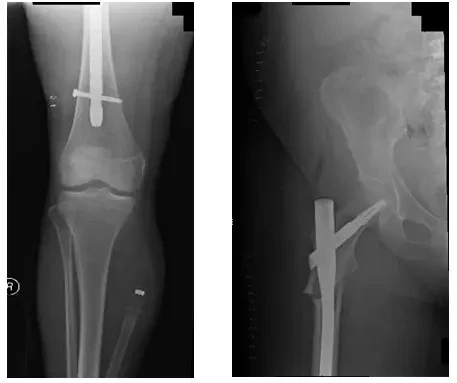

Les radiographies postopératoires montrent une fixation interne à réduction ouverte (ORIF) du fémur droit.

Les radiographies montrent une tige intramédullaire s’étendant du grand trochanter, à travers la fracture fémorale proximale, jusqu’à la tige distale du fémur où il y a une vis horizontale.